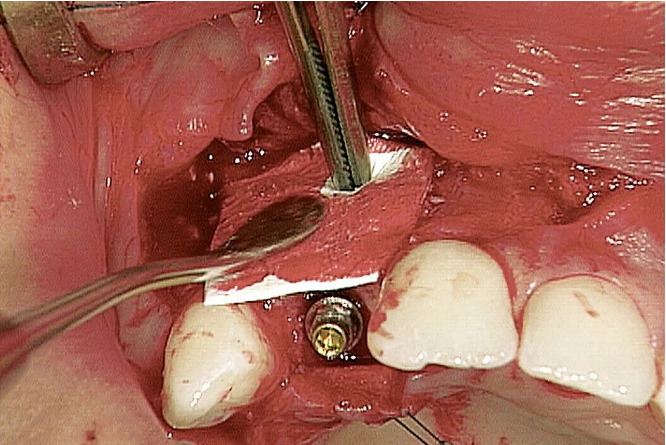

图片左侧: Geistlich Bio-Oss® 与人体骨非常相似(放大倍数50倍)。图片右侧: 人体骨的独特结构 (放大倍数50倍)。 Geistlich Bio-Oss® 颗粒的超级多孔结构有助于新骨形成。(放大倍数:5000倍) 术后9年:新骨直接接触Geistlich Bio-Oss® 颗粒。骨在骨小梁结构与Geistlich Bio-Oss® 之间、无机骨基质之间形成桥梁结构。 Geistlich Bio-Oss® 的成骨效果好,提升种植体存活率4,5 Geistlich Bio-Oss® 方便操作,且临床适应症非常广泛 Geistlich Bio-Oss® 已经在临床领域成功应用了25年,目前有超过700篇科学研究文献 “ 盖氏产品多年以来深得我信赖。” PROF. MARIANO SANZ, 西班牙马德里 十九世纪八十年代,Dr. Peter Geistlich突破性地将有机成分从骨材料中除掉,而又不破坏其自然微观结构和骨组成。如今,Geistlich Bio-Oss® 已经被认为是口腔骨再生领域中先进的骨替代材料——满足临床医生对预期疗效的需求。 Geistlich Bio-Oss® 操作简单 Geistlich Bio-Oss® 具有良好的易操作性及始终如一的临床优异表现。 使用前,将Geistlich Bio-Oss® 和血液或生理盐水混合。它的亲水性促进迅速、彻底的水合。 Geistlich Bio-Oss® 易于构建成骨空间,并黏附于骨壁缺损处。 切勿过度挤压,要为新骨形成留出足够的空间。 配合胶原膜使用,如Geistlich Bio-Gide® ,能获得更好的骨再生疗效。 在容器中将Geistlich Bio-Oss® 与缺损区渗出血液或生理盐水混合。颗粒间具有很好的粘附性。 Geistlich Bio-Oss® 易成型,为给新骨生成留出空间,不需要用力按压。 在植骨区上覆盖Geistlich Bio-Gide® ,以确保新骨生成不受干扰。 Geistlich Bio-Oss® 大小颗粒共有五种规格适用于骨缺损。 可以很好地覆盖周围的表面轮廓。 特别适用于小面积缺损和自体骨移植的轮廓填充。 有以下规格: 0.25 g ~ 0.5 cc 0.5 g ~ 1 cc 2 g ~ 4 cc